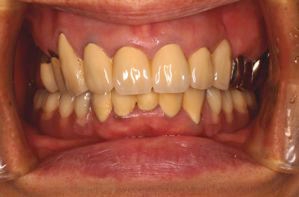

両側5歯症例

両側5歯症例両側5歯症例両側5歯症例 主訴-義歯のバネが壊れて手前の歯が痛んできた。 術前(旧義歯装着、鏡像) 術前(下顎粘膜面、鏡像)術前(下顎粘膜面、鏡像)術前(下顎粘膜面、鏡像) 術前レントゲン術前レントゲン術前レントゲン 術前口腔内(正面観)術前口腔内(正面観)術前口腔内(正面観)